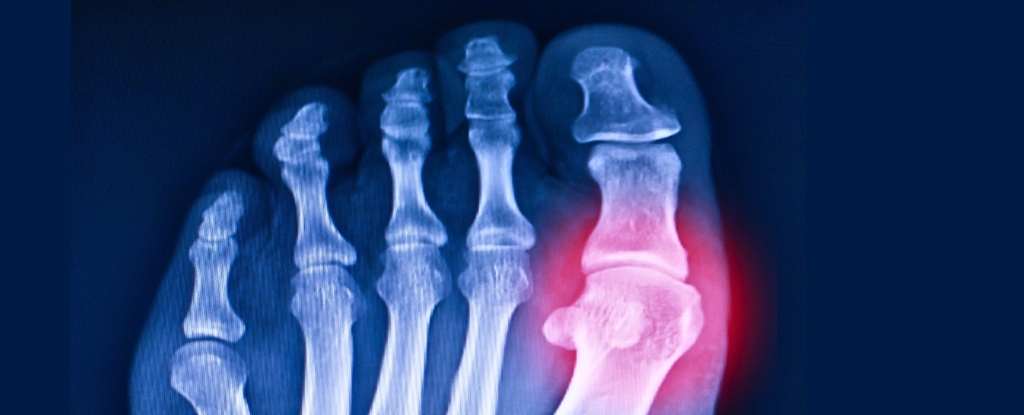

High uric acid levels, which can cause gout and joint pain, are often triggered by certain foods rich in purines. To manage and prevent symptoms, it is recommended to avoid red meats, organ meats, certain seafood, processed foods, alcohol, excessive lentils, sugary drinks, and high-fat dairy products. Making dietary and lifestyle changes can significantly reduce flare-ups and long-term health risks.